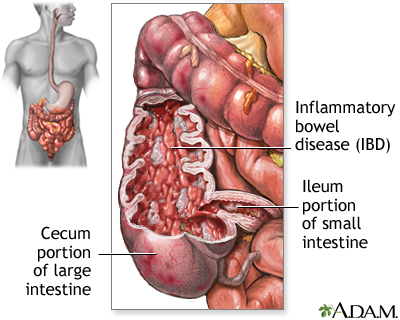

Crohn disease is a disease where parts of the digestive tract become inflamed.

- It most often involves the lower end of the small intestine and the beginning of the large intestine.

- It may also occur in any part of the digestive system from the mouth to the end of the rectum (anus).

Crohn disease is a form of inflammatory bowel disease (IBD).

When parts of the digestive tract remain swollen or inflamed, the walls of the intestines become thickened.